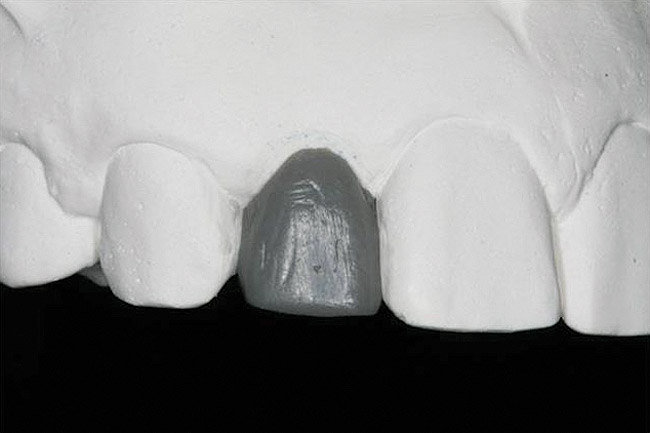

Figure 14 Exploiting study casts for planning single-tooth implant placement and restoration: Mounted study casts permit an estimation of available bone volume (Fig 13); measure the bound edentulous space inter-tooth dimensions (Fig 14); measure the avail

Figure 14

Figure 15 Exploiting study casts for planning single-tooth implant placement and restoration: Mounted study casts permit an estimation of available bone volume (Fig 13); measure the bound edentulous space inter-tooth dimensions (Fig 14); measure the avail

Figure 15

Figure 16 Exploiting study casts for planning single-tooth implant placement and restoration: Mounted study casts permit an estimation of available bone volume (Fig 13); measure the bound edentulous space inter-tooth dimensions (Fig 14); measure the avail

Figure 16

The exploration of this architecture is only fully achieved by evaluation of study casts that clearly reveal the detailed anatomy of the alveolus and the peri-coronal tissues. Study casts should be mounted in maximum intercuspal position for the complete treatment planning of single-tooth dental implants. Mounted casts enable estimation of the required 6 mm of space between the ridge crest (approximately 2 mm submucosal) and the opposing tooth and measurement of the mesiodistal interdental distance. The orientation of the implant in the alveolus should neither interfere with the required occlusion nor should it obviate the placement of an esthetic crown (eg, excessively buccal orientation). This can be revealed through the diagnostic waxing process. Encroachment of opposing teeth into the bound edentulous space may suggest the need for possible adjustment or orthodontic movement of the antagonist. When excellent study casts are mounted, it is possible to: estimate bone volume; measure bound edentulous space inter-tooth dimensions; measure inter-arch dimensions; and evaluate alveolar ridge/tooth relationships (superseding resorbed ridge classification) (Figure 13 through Figure 16).